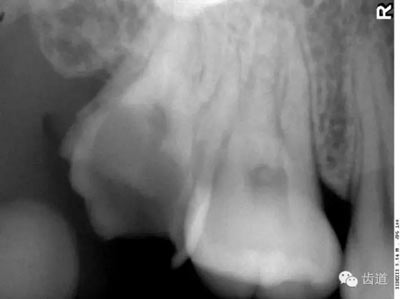

在投照上頜磨牙根尖片時,經(jīng)??梢钥吹窖栏戏接幸幻芏鹊偷挠跋?,為上頜竇的一部分,邊緣環(huán)繞以密度高的線狀影像,為上頜竇壁致密骨層。有時可見上頜竇的分隔。

可在第一、二磨牙根尖上方或重疊在牙根上為近似三角形或半圓形密度高的影像。

常在上頜第二、三磨牙的牙冠區(qū)域有一較牙密度稍低由后伸向前方的三角形影像。

在最后一個磨牙遠(yuǎn)中區(qū)域,其邊緣向后上,X線片上常呈稀疏的網(wǎng)狀結(jié)構(gòu),為正常疏松區(qū)。

在上頜結(jié)節(jié)后方,呈長條狀邊緣整齊、寬約0.2cm、長約1cm、直的或下端略向后方彎曲的密度稍高的影像。

在第一磨牙腭側(cè)根上方呈圓形密度低影像。